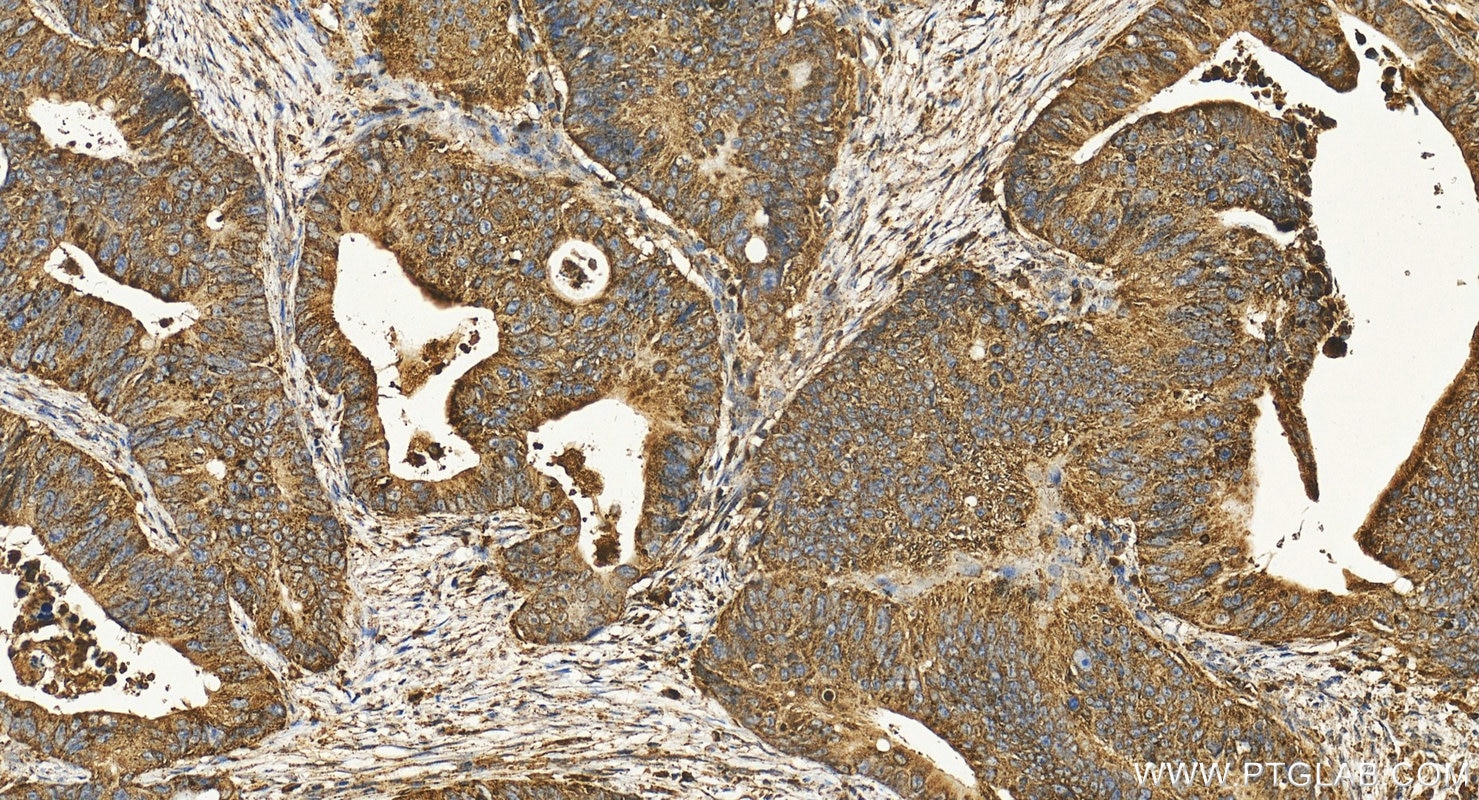

| Positive IHC detected in | human colon cancer tissue, human gliomas tissue, human liver cancer tissue, human pancreas tissue, human placenta tissue Note: suggested antigen retrieval with TE buffer pH 9.0; (*) Alternatively, antigen retrieval may be performed with citrate buffer pH 6.0 |

LAMP1 (also known as CD107a) is a 90-120 kDa heavily glycosylated membrane protein enriched in the lysosomal membrane. LAMP1 functions to provide selectins with carbohydrate ligands. This protein has also been shown to be a marker of degranulation on lymphocytes such as CD8+ and NK cells and may also play a role in tumor cell differentiation and metastasis.